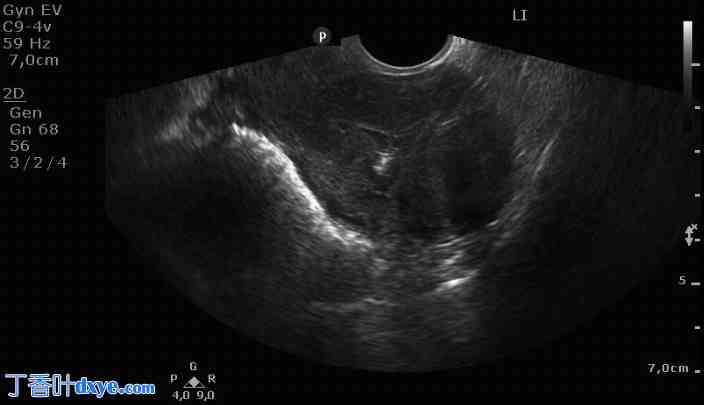

术后三个月经阴道超声检查发现一个大小为23×36×32毫米的宫内子宫肌瘤(图2)。经宫颈消融术后,黏膜下子宫肌瘤显著缩小,并似乎已完全排出宫腔。由于既往宫腔镜检查时疼痛剧烈,选择在手术麻醉下进行诊断性宫腔镜检查,如果条件允许,可在同一次检查中立即进行宫腔镜治疗性切除子宫内肌瘤。宫腔镜检查结果显示,子宫肌瘤为FIGO 0型,呈萎缩性外观(图3)。

图2. 经阴道超声显示,经Sonata系统治疗后,肌瘤缩小并排出宫腔。